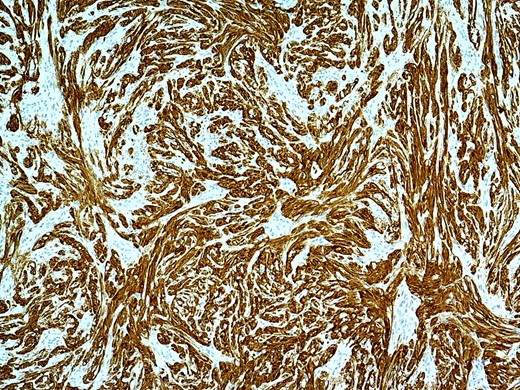

Microscopically, there was an unencapsulated, round tumour centred on the submucosa and muscularis propria. The tumour was composed of fascicles of spindle cells, including some palisading of nuclei (Verocay bodies), however, no significant atypia and no mitoses are seen. The tumour was strongly positive for S100. A diagnosis of Schwannoma was made.

Mucosal biopsies are often inconclusive as the tumour lies in submucosa. Deep submucosal biopsies or submucosal resections can differenciate it from other submucosal GI Tumours like GISTs, neuro-endocrine tumours and leiomyomas [2, 9]. Definitive diagnosis is by immunohistochemistry as they stain strongly positive for S100. It is essential however to confirm the diagnosis of schwannoma as the other differentials like GISTs have much higher malignant potential and can recur.